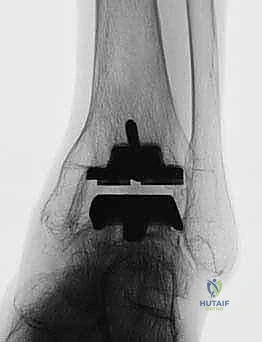

FIG 6 • The TNK ankle replacement for rheumatoid arthritis of the ankle (cemented replacement). A. Preoperative AP view. B. Preoperative lateral view. C. Postoperative AP view 2 years 6 months after the surgery. D. Postoperative lateral view.